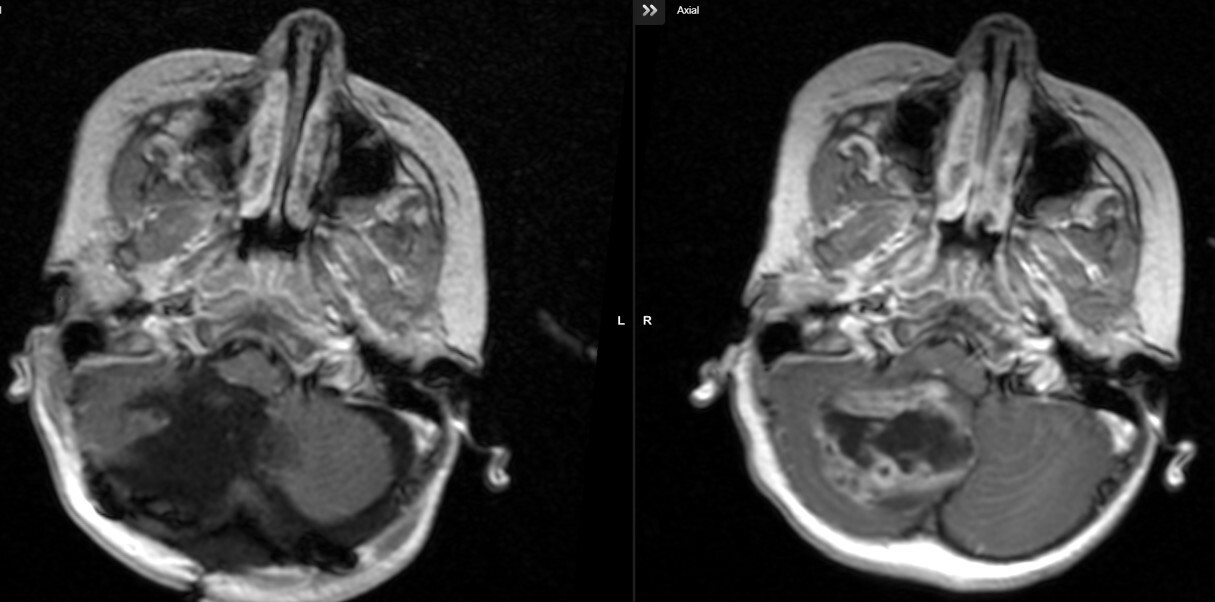

Η ασθενής υποβλήθηκε σε MRI εγκεφάλου, η οποία αποκάλυψε:

- Χωροκατακτητική εξεργασία στον οπίσθιο κρανιακό βόθρο.

- Σοβαρά πιεστικά φαινόμενα στην παρεγκεφαλίδα και το στέλεχος.

- Δευτεροπαθή αποφρακτικό υδροκέφαλο.

- Επείγουσα Επεμβατική Φάση: Πραγματοποιήθηκε ενδοσκοπική τρίτη κοιλιοστομία (ETV) για την άμεση αποσυμφόρηση του υδροκεφάλου και τη ρύθμιση της ενδοκράνιας πίεσης.